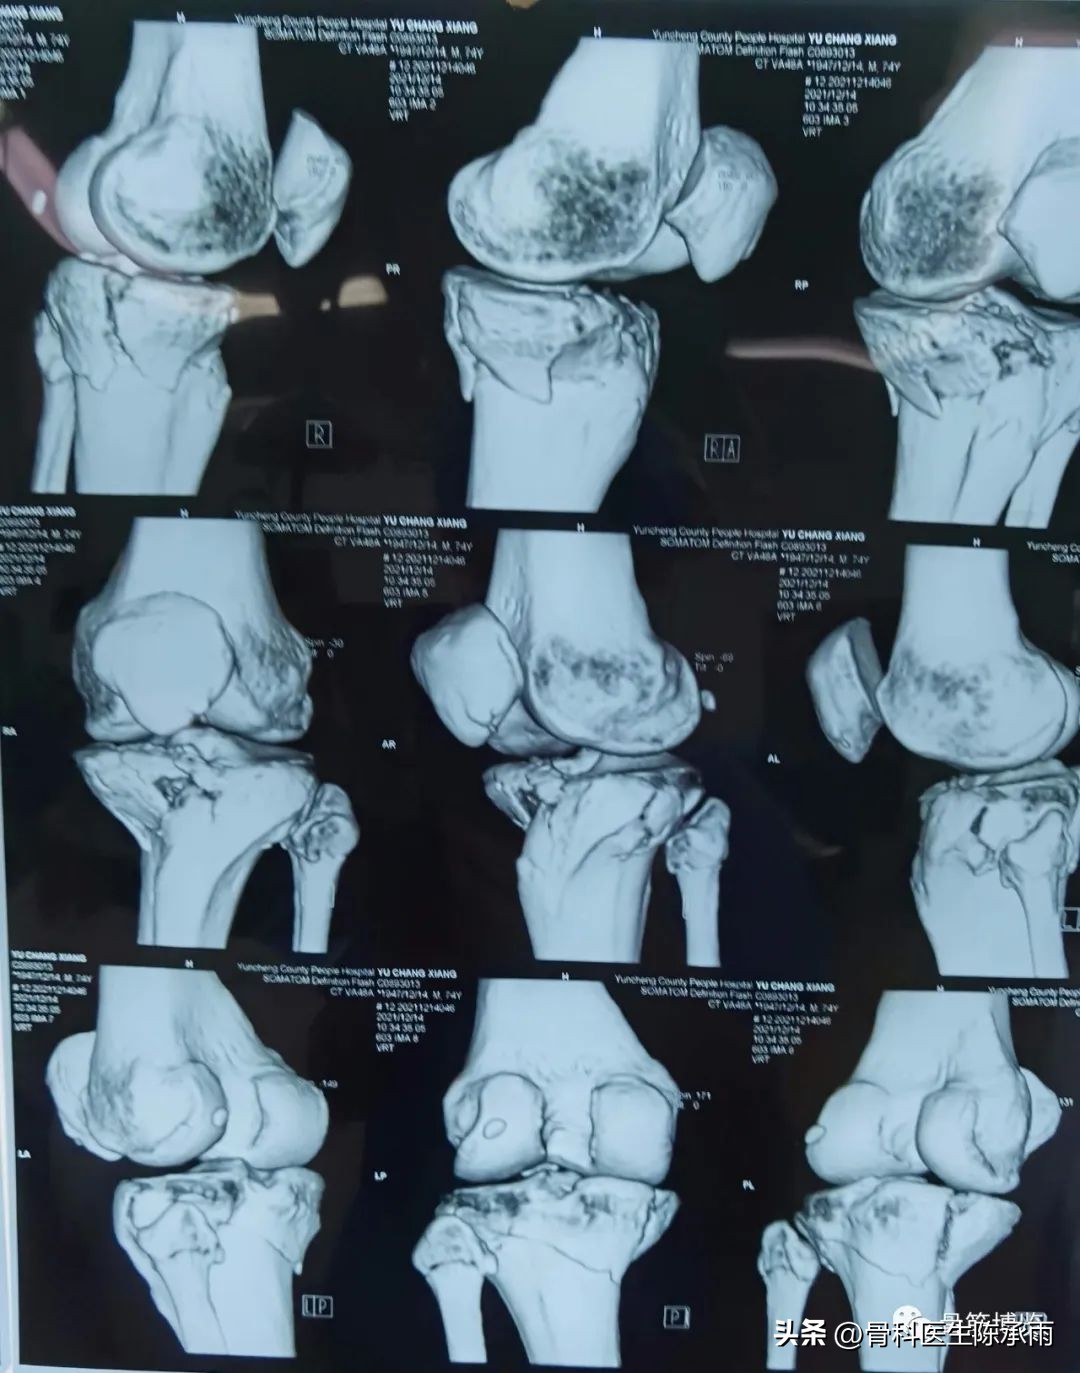

胫骨平台骨折的分型比较多,我们临床上常用的就是Schatzker分型和AO骨折的分型,还有骨折脱位的Hohi-Moore分型,这是我们常用的三个分型。

Schatzker分型来讲它一共分为六型:

一型 劈裂,

二型 劈裂塌陷,

三型 外髁的一个单纯塌陷,

四型 内髁的骨折,

五型 双髁的骨折,

六型 双髁伴干骺端的骨折,

对AO 分型来讲,现在这是AO推出来更详细的,再分为ABC。随着分型的增加,从A到C骨折的损伤程度是越来越重,治疗也越来越困难,从1到2 ,123也是这个规律,骨折的分型就是给我们表明了骨折的一个损伤的程度,治疗办法和损伤的特点。我们对于骨折脱位的分型,常用Hohi-Moore分型,这个是弥补了,Schatzker和AO分型的一些缺陷。

1例

2例

3例

4例

5例

6例

7例